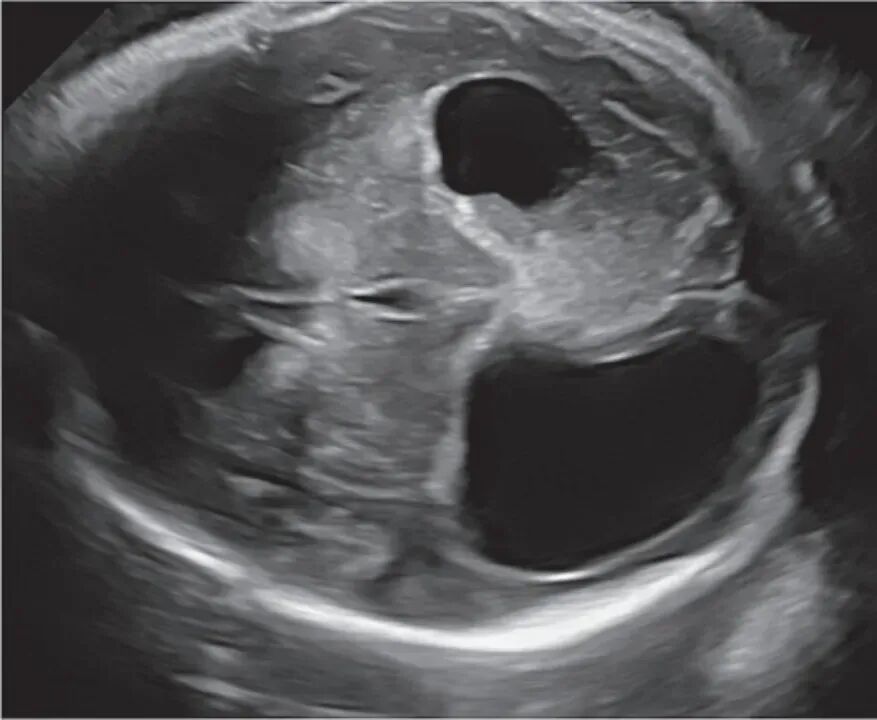

一名33岁初产妇,孕36周常规超声生长发育检查时,发现胎儿双侧及第三脑室严重扩张,脑实质病变,但生长发育正常。